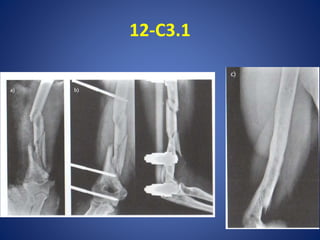

12-C3.1

• #38 En este ejemplo se decidio estabilidad absoluta con lcp…compresion a través de la placa con tornillos , ademas utilizacion de tornillos bloqueados….tener en cuenta 6 corticales proximales- 6 corticales distales